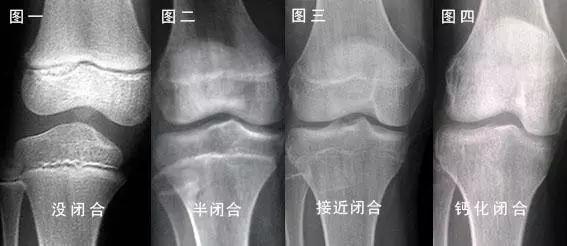

首先,我们先来普及下人类长高的关键,在是一个叫做「骨骺」的部位。骨骺就像腿骨上的盖子,一旦闭合,人也就没法长高了。

人类骨骼生长的一般规律,人在生长期的时候,骨是由骨干和骨骺端两部分构成的,骨干是骨的中间部位。骨骺端长在骨干的两头,人在刚出生的时候是没有骨骺端这个结构的,随着人的成长在持续。骨骺端出现,并逐渐生长,先开始变宽,后开始变厚 ,然后逐渐硬化,与骨干逐渐长在一起变成成熟的骨组织。

一般来说,股骨上端的骨骺闭合最早,约在 16~18 岁左右;股骨下端和胫骨上端的骨骺闭合晚,约在 19~24 岁左右。